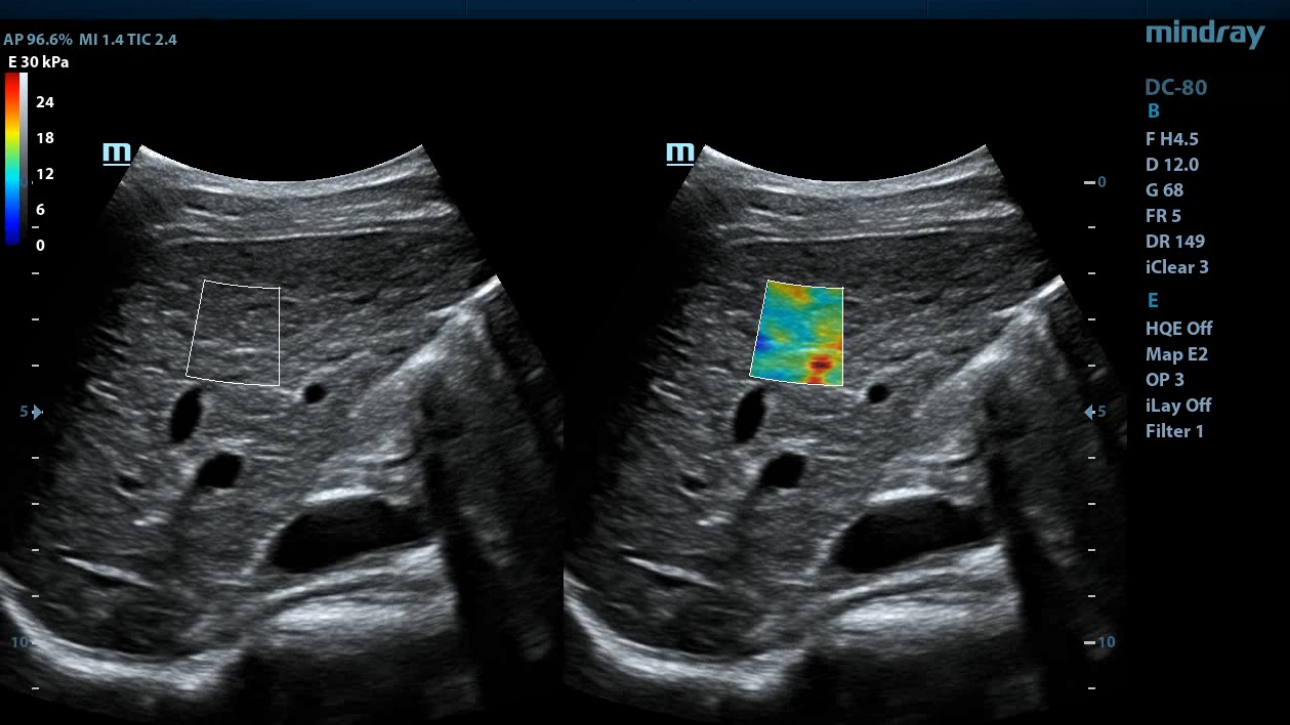

eXceptional Intelligence

Intelligence throughout entire workflow

Intelligence integrated in professional diagnostic tools for whole examination procedures,DC-80 with X-Insight provides exceptional intelligence integrated in professional diagnostic tools across wide applications and throughout whole examination procedures, from regular screening to further diagnosis and clinical follow up.